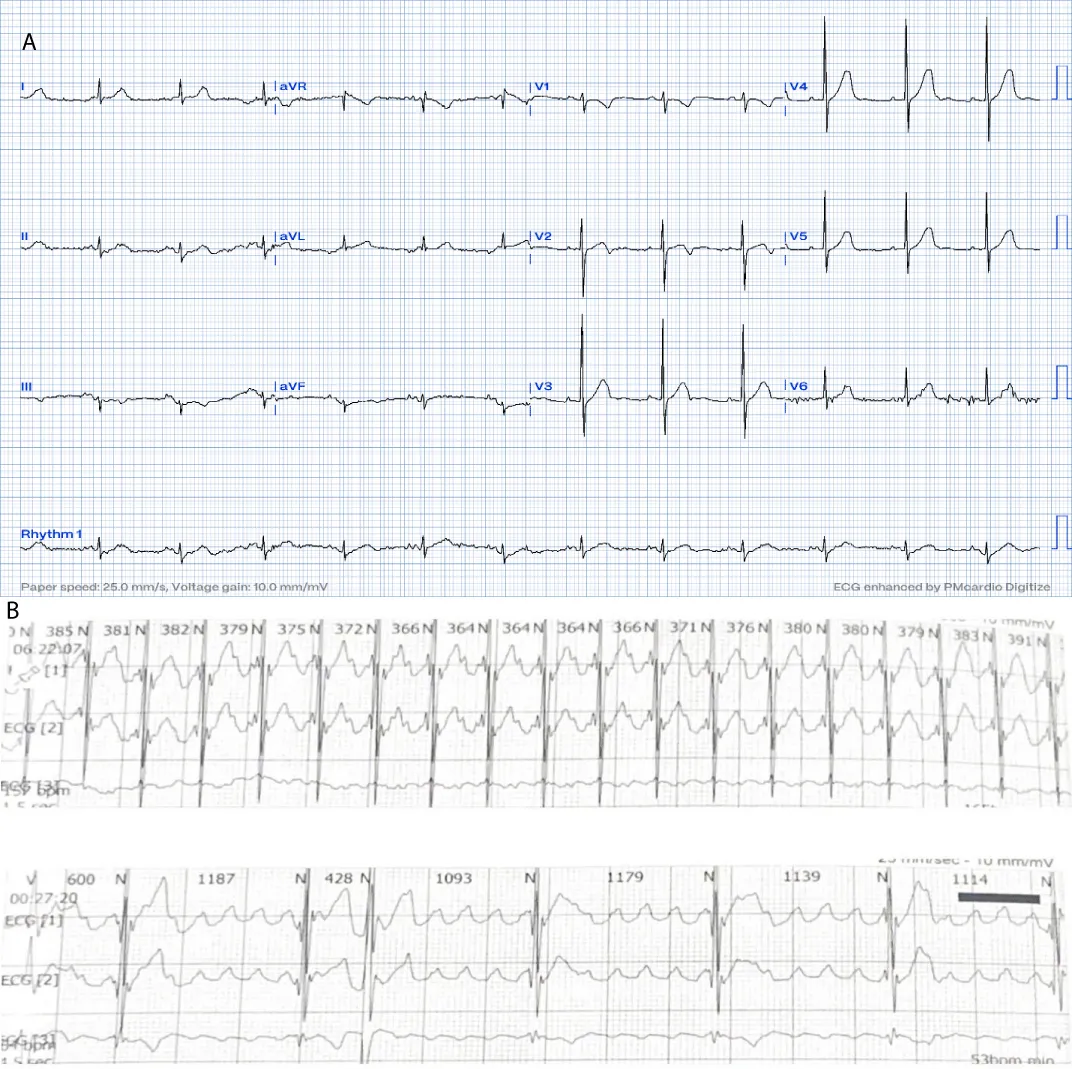

A 16-month-old child with no past medical history, referred for bradycardia. She was clinically asymptomatic except for poor growth consistent with weight and height below the third percentiles. Her ECG (Figure 1A) revealed left axis deviation, normal PR interval but with significant bradycardia indicative of Sinus Node Dysfunction (SND). Her echo revealed a small ASD but was otherwise normal. The Holter (Figure 1B) showed persistent atrial flutter (AFL), with variable degrees of block (2:1 - 6:1) and heart rates (HR) between 53-150 beats per minute (bpm). The average HR was 92 bpm despite being not on any atrioventricular nodal (AVN) blocking agent, raising concerns about intrinsic AVN dysfunction. The patient was admitted (Figure 2) for TEE to rule out intracardiac thrombi and subsequent cardioversion. She was successfully reverted to sinus rhythm, but remained bradycardic, and was started on low-dose Sotalol, at 1 mg/kg/ day, given the intrinsic conduction disease. Maternal ECG was normal, but a paternal one could not be obtained, and genetic testing was refused. Family history was otherwise unremarkable. Two months later, a follow-up Holter revealed counterclockwise AFL for which she was admitted and again cardioverted successfully. Sotalol was increased to 1.5 mg/kg/day. Over the next four months, two follow-up Holter ECGs (Figure 3) showed junctional and ventricular escape rhythms with rare sinus capture beats. Two months later, the patient came back with AFL and underwent successful cardioversion (Figure 4). The family was offered either pacemaker implantation or ablation, but initially refused both. At this point, the dose of Sotalol was increased to 2 mg/kg/day. One month later, the patient returned with persistent AFL, underwent successful cardioversion, and agreed to proceed with ablation. A zero-fluoroscopy, dual-catheter electrophysiology study (EPS) was performed using 7F Freezor™ Xtra cardiac cryoablation catheter (217F1 – 49 mm), at the age of 2 years and 10 months (9 kg). The EPS demonstrated cavotricupsid isthmus based typical AFL (proved with entrainment), and cryoablation of the isthmus resulted in termination of AFL (one application for 2 minutes per location, point by point across cavotricuspid isthmus). After ablation and while not on sotalol, the rhythm was predominantly junctional rhythm, but no recurrence of flutter was observed over the subsequent 12 months. The patient is currently approaching 4 years of age.

Figure 1: At the time of presentation. 1A: ECG shows bradycardia, left axis deviation, and negatively deflected P-waves in leads I and AVL suggesting left upper atrial focus.